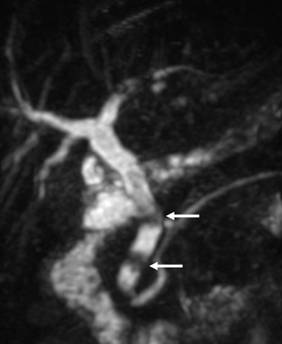

У %) больных при поступлении выявляли осложнения, сопутствующие механической желтухе (табл.2). Наиболее часто диагностировали печеночно-почечную недостаточность (15,79%) у пациентов с длительно существующей билиарной гипертензией и высокими цифрами билирубина, сопровождающуюся гемокоагуляционными расстройствами и энцефалопатией. Сопутствующий механической желтухе холангит, который диагностирован у,53%) больных, рассматривали как патологическое состояние, проявляющееся местным инфекционным воспалением желчных путей и системной воспалительной реакцией (СВР) с высоким риском перехода в билиарный сепсис [5]. При длительном существовании гнойного холангита у 7 (2,83%) пациентов выявлены холангиогенные абсцессы печени. Главной причиной их развития явились рубцовые стриктуры желчных протоков (Рис. 3) у 3 и длительно существующий холедохолитиаз (Рис. 4) у 4 пациентов. Одним из наиболее опасных осложнений механической желтухи, требующих экстренных хирургических манипуляций, считаем билиарный панкреатит, выявленный у,74%) пациентов, причиной развития которого являлся ущемленный камень БДС и спазм или стеноз сфинктера Одди (Рис. 5). При опухолях БДС и стойком нарушении оттока желчи билиарный панкреатит наблюдали лишь в 2 случаях (Рис. 6). Наиболее частыми признаками билиарного панкреатита были: боль, наличие интоксикационного синдрома с быстрым развитием гемодинамических расстройств. Желтуха при билиарном панкреатите носила, как правило, смешанный характер. [6,17].

Рис. 4 МРХПГ. Дефекты наполнения (конкременты) в просвете общего печеночного и общего желчного протоков.